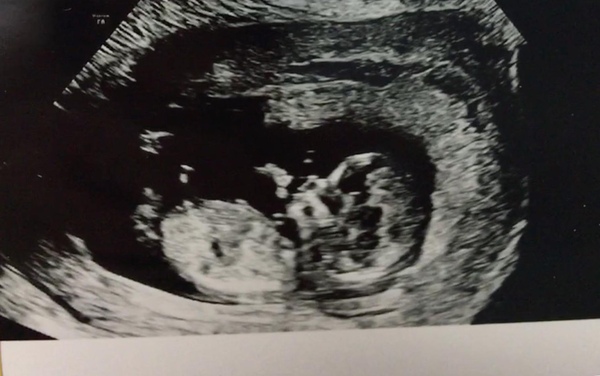

Here’s my picture ❤️ Baby was just putting hand to mouth. Everyone is saying girl but I’ve no idea! X